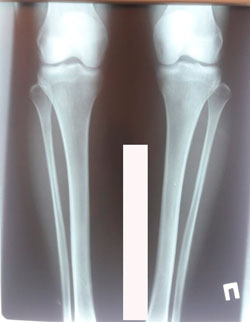

Исходник 37 лет.

Дата операции - 13.05.2020

image-21-05-20-08-15-3.jpg

image-21-05-20-08-15-1.jpg